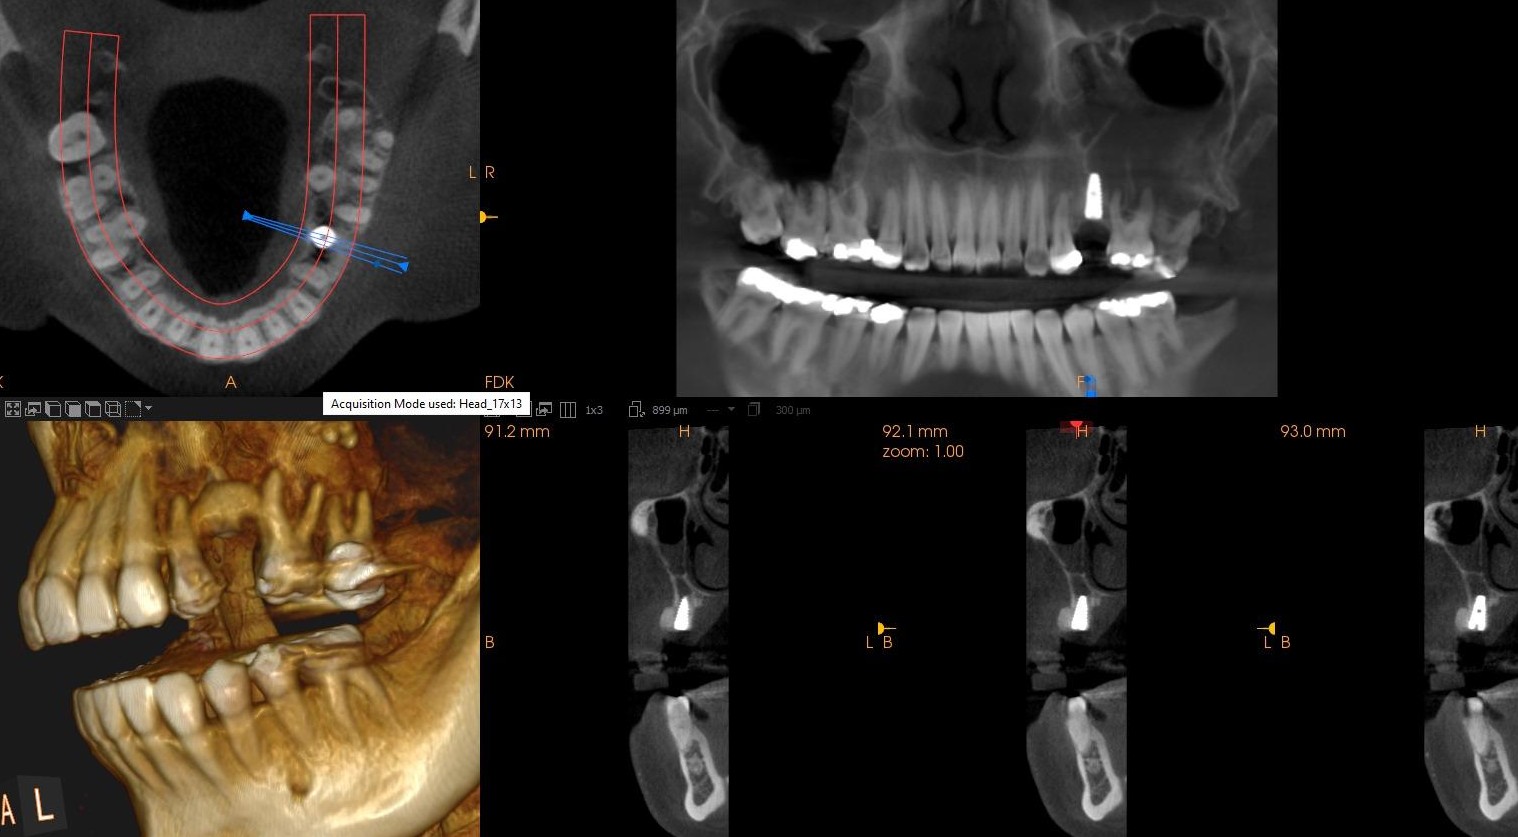

INITIAL STATE

Clinical and radiographic examination revealed a failed implant with signs of periimplant tissue compromise. Intraoral evaluation demonstrated inadequate soft tissue quality and unfavourable conditions for immediate restoration. CBCT imaging was performed to assess bone volume, implant position, and anatomical limitations prior to treatment planning.